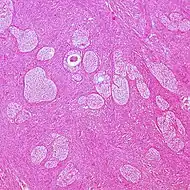

| Type | Subtype | Relative incidence[2] | Percent malignant[2] | Comments | Micrograph |

| Surface epithelial-stromal tumor | Serous tumor | 25% | 18.5% | Benign serous tumors of the right ovarian cyst are thinwalled unilocular cysts that are lined by ciliated pseudostratified cuboidal or columnar epithelium.[6] | ![]() |

| Mucinous tumor | 15% | 8.8% | Benign mucinous tumors of the ovary consist of simple, nonstratified columnar epithelium with basally-located hyperchromatic nuclei and resemble gastric foveolar epithelium.[6] | ![]() | |

| Endometrioid tumor | 1% | Almost 100% | Tubular glands, resembling endometrium.[7] | ![]() | |